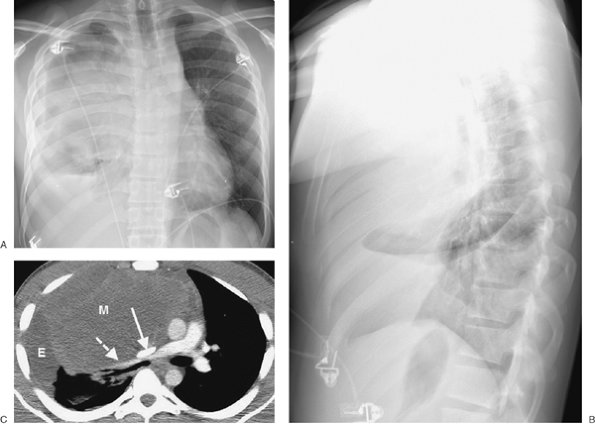

FIGURE 6-16. Benign teratoma. A: PA chest radiograph shows abnormal opacity in the right hemithorax, some of which is caused by pleural effusion, and mediastinal shift to the left. B: Lateral view shows abnormal opacity in the retrosternal area. C: CT scan shows an anterior mediastinal mass of homogeneous soft tissue attenuation (M), compressing a narrowed superior vena cava (solid arrow) and right pulmonary artery (dashed arrow), and right pleural effusion (E).